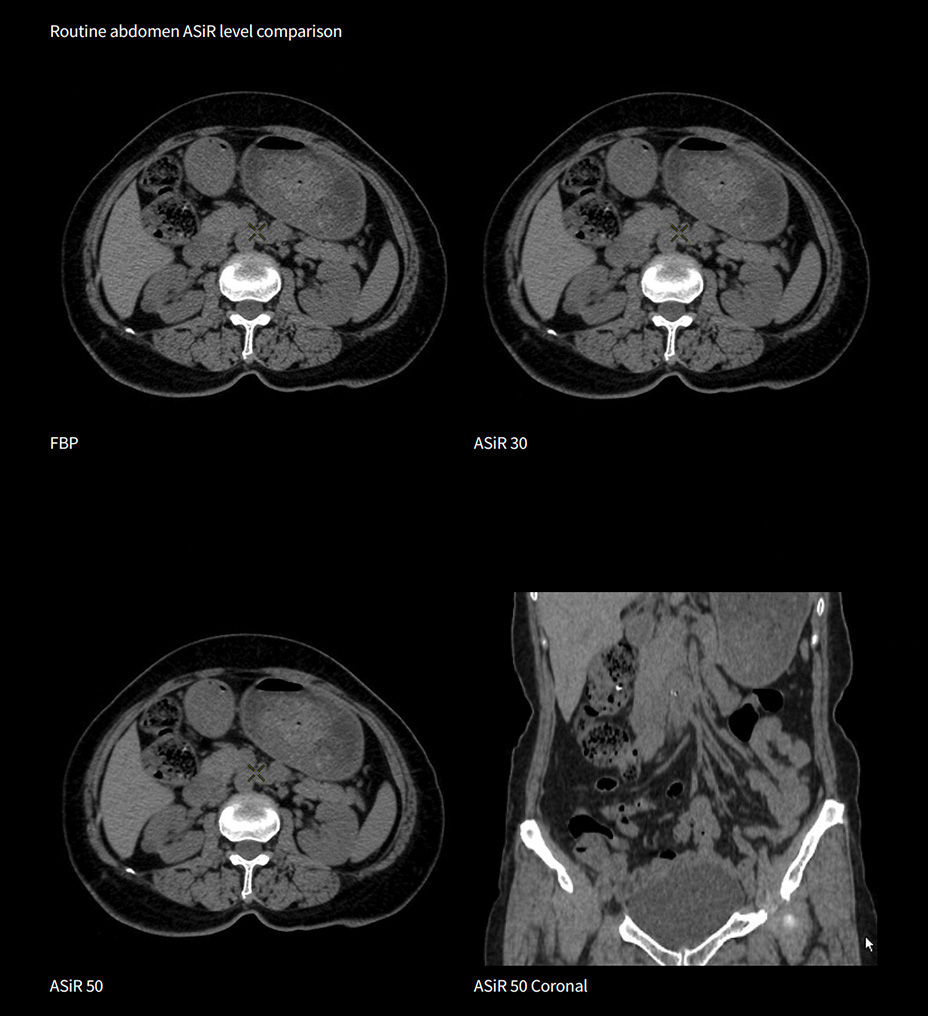

At the heart of Revolution Advance is a high-performance, reliable imaging chain with 42 kW of generator power, a 3.5 MHU X-ray tube and integrated detectors that reduce signal-to-noise by 20%2. This is paired with our smart, dose-reducing reconstruction applications like ASiR2, which can provide up to 40% lower dose while maintaining high image quality2.